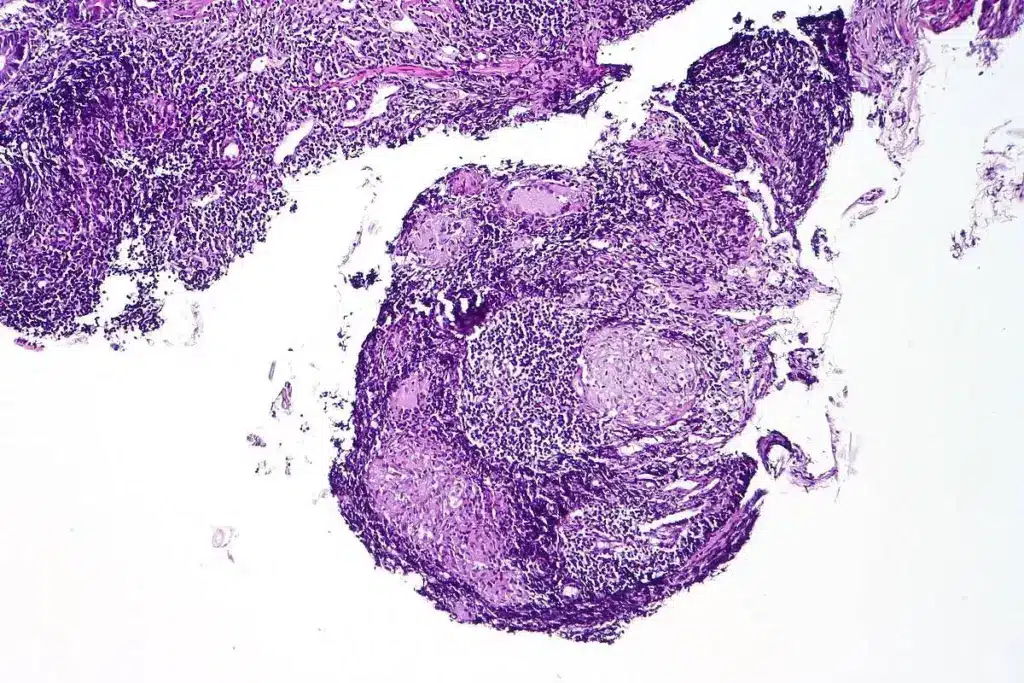

How Biopsy Procedures Detect Skin Cancer

Biopsy procedures are key in finding skin cancer. They give a clear diagnosis that helps decide how to treat it. By looking at a skin tissue sample, doctors check for abnormal cell growth.

Basal Cell Carcinoma Characteristics

Basal cell carcinoma (BCC) is the most common skin cancer. It grows slowly and doesn’t hurt. Histopathological examination through biopsy shows basaloid cells with peripheral palisading. BCC is not usually deadly but can damage the skin if not treated.

Squamous Cell Carcinoma Features

Squamous cell carcinoma (SCC) is another common skin cancer. It can grow deep into the skin. Biopsy shows keratinization and atypical squamous cells. SCC can spread, so finding it early is important.

Melanoma Identification and Staging

Melanoma is the most dangerous skin cancer. It comes from melanocytes. Biopsy checks the Breslow thickness and for ulceration. Immunohistochemistry helps confirm it. Knowing the stage is key for treatment and outlook.